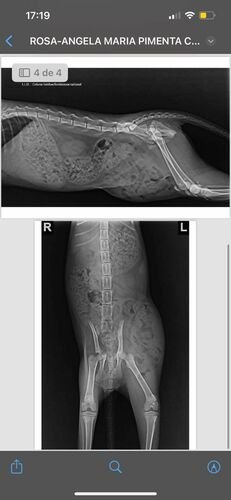

Ela foi atropelada, abandonada e recebemos o pedido de ajuda! Resgatamos…ela passou pelo vet e fez um raio-x, no qual foi visto fratura do quadril em 2 lugares e rompimento do abdômen!!! O INTESTINO foi parar na PERNA e ela corria RISCO DE MORTE!

Ela passou por cirurgia para corrigir a abertura do abdômen e já foi realizada a castração…o vet optou por não corrigir as fraturas do quadril devido à complexidade da cirurgia e por ter chance de calcificar pela idade, mas infelizmente pode ser que ela fique “tortinha” e até tenha dores pro resto da vidinha dela…